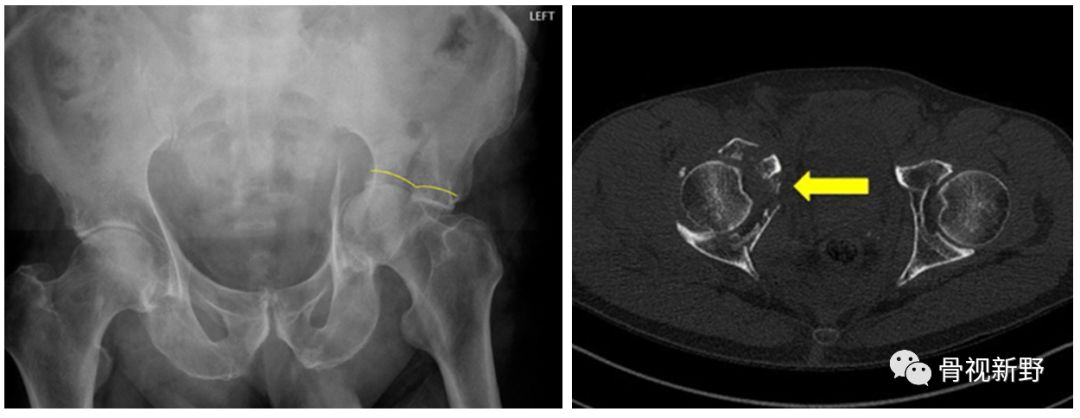

股骨颈骨折的medial buttress

垂直型股骨颈骨折(Pauwels III型)常因垂直剪力大、常规三枚平行空心钉固定易致内固定失败,单纯空心钉+第四枚垂直螺钉或medial buttress 钢板可起到对抗垂直剪力的防滑、支撑作用。

股骨颈内侧的防滑、支撑(Medial buttress)

Medial buttress是指在股骨颈骨折解剖复位、平行拉力钉常规加压后,于股骨颈下内侧、放置一块3-4孔三分之一管型钢板、重建钢板或其它微型钢板,在紧靠骨折尖下方打入一枚穿过双层皮质的防滑螺钉(Buttress screw),再在远、近侧根据情况打入第二枚或更多螺钉。这样,通过钢板的支撑作用可将骨折断端间的垂直剪切力转化为利于骨折愈合的压应力。这种应力转化有利于预防垂直型不稳定股骨颈骨折常见的内翻塌陷及不愈合并发症[Mir 2015]。